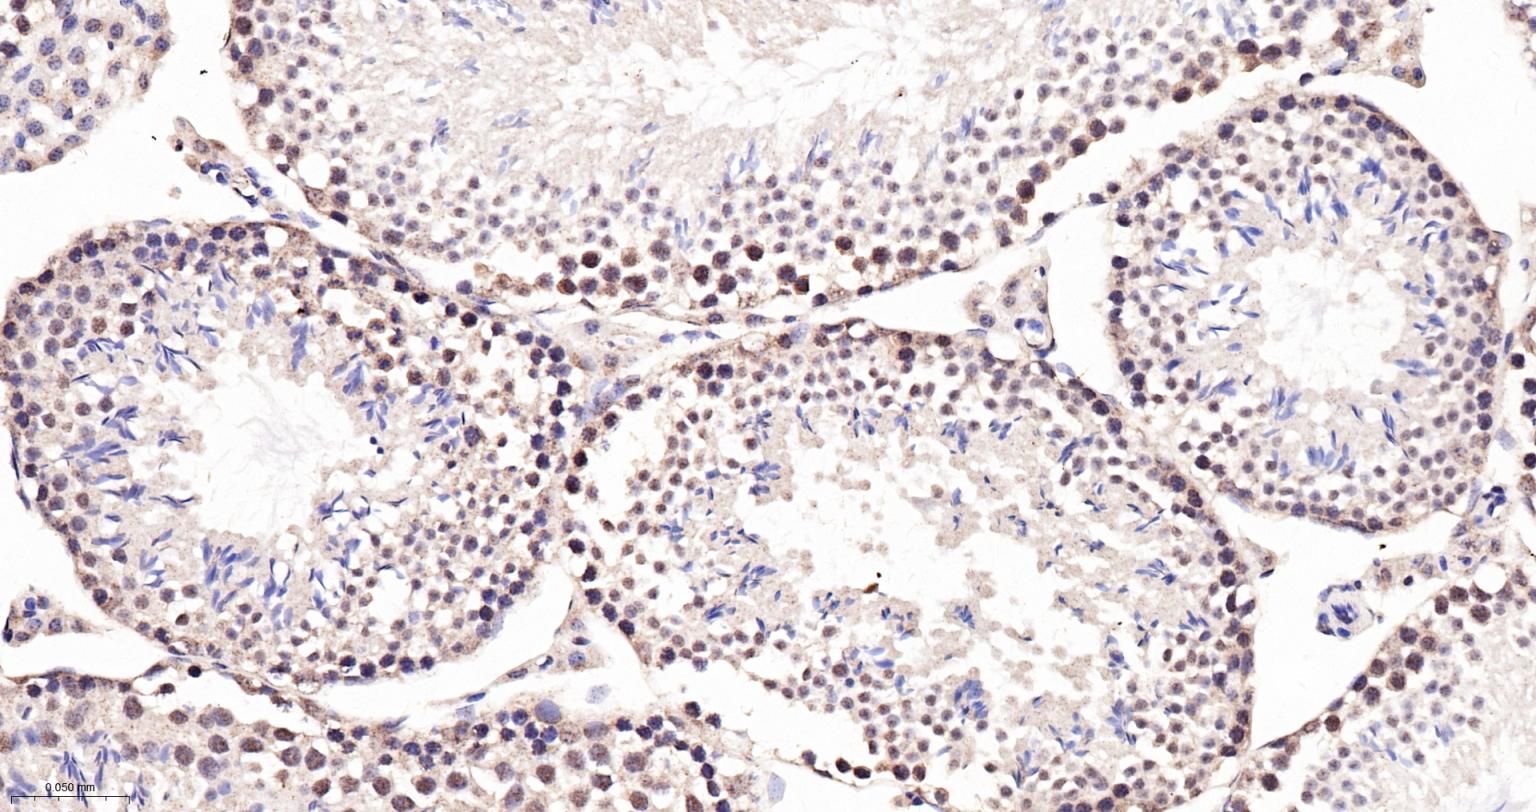

Paraformaldehyde-fixed, paraffin embedded Rat Thymus; Antigen retrieval by boiling in sodium citrate buffer (pH6.0) for 15 min; The section was incubated with MAD2L1BP Monoclonal Antibody, Unconjugated (bsm-61271R) at 1:200 overnight at 4°C, followed by conjugation to the bs-0295G-HRP and DAB (C-0010) staining.